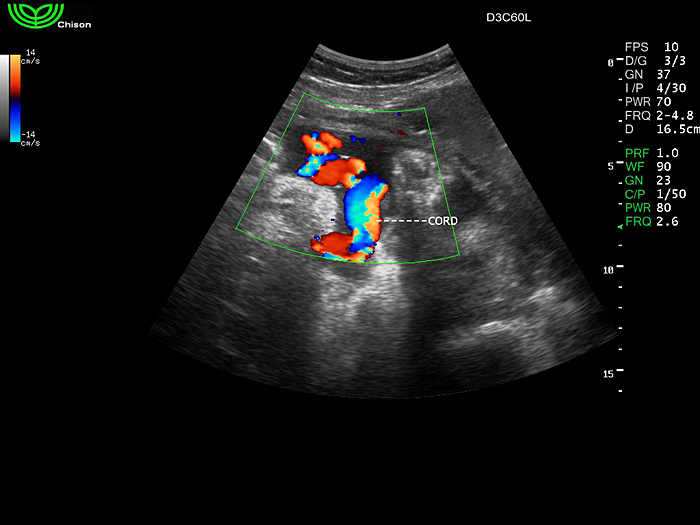

D3C60L 3.5МГц, конвексный.

2.0МГц - 5.8 МГц. Применения: абдомиальное обследование, акушерство, гинекология, обследование районной блокады нерва, осуществление и управление биопсией. |